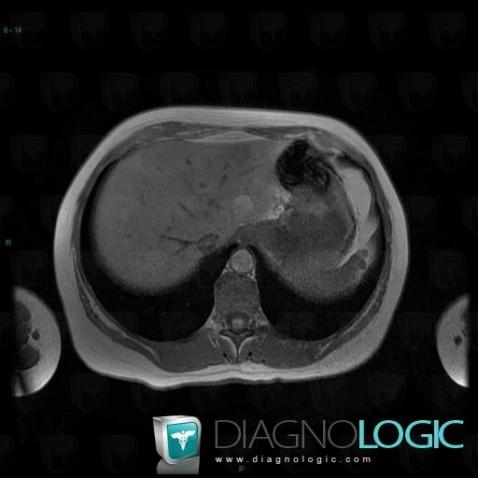

Focal fatty change, Liver, MRI

Here is the specific information in the key image above:

- Diagnosis Focal fatty change, Location(s) Liver, with gamuts T1 WI hyperintense hepatic lesion